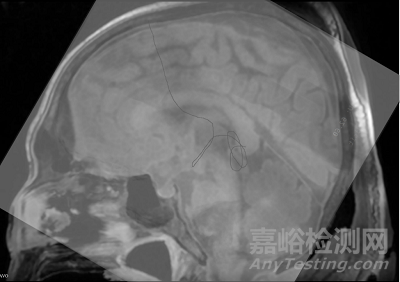

并使用基于MRI圖像的術(shù)前計(jì)劃,MicroNeuro以侵入性最小的方式通過(guò)自然腦腔到達(dá)目標(biāo)位置。

手術(shù)前MRI圖像與手術(shù)后X光對(duì)比結(jié)果表明,機(jī)器人的柔性內(nèi)鏡末端成功抵達(dá)第三腦室松果體區(qū),充分驗(yàn)證了使用MicroNeuro在第三腦室與側(cè)腦室手術(shù)的可行性,展示了該機(jī)器人良好的運(yùn)動(dòng)控制精度。

MicroNeuro成功經(jīng)彎曲的腦室腔道抵達(dá)第三腦室底部,并進(jìn)行活檢取樣。在退出過(guò)程中,MicroNeuro同時(shí)釋放0.2mm鎳鈦絲,以標(biāo)記柔性內(nèi)鏡行進(jìn)軌跡,證明手術(shù)成功